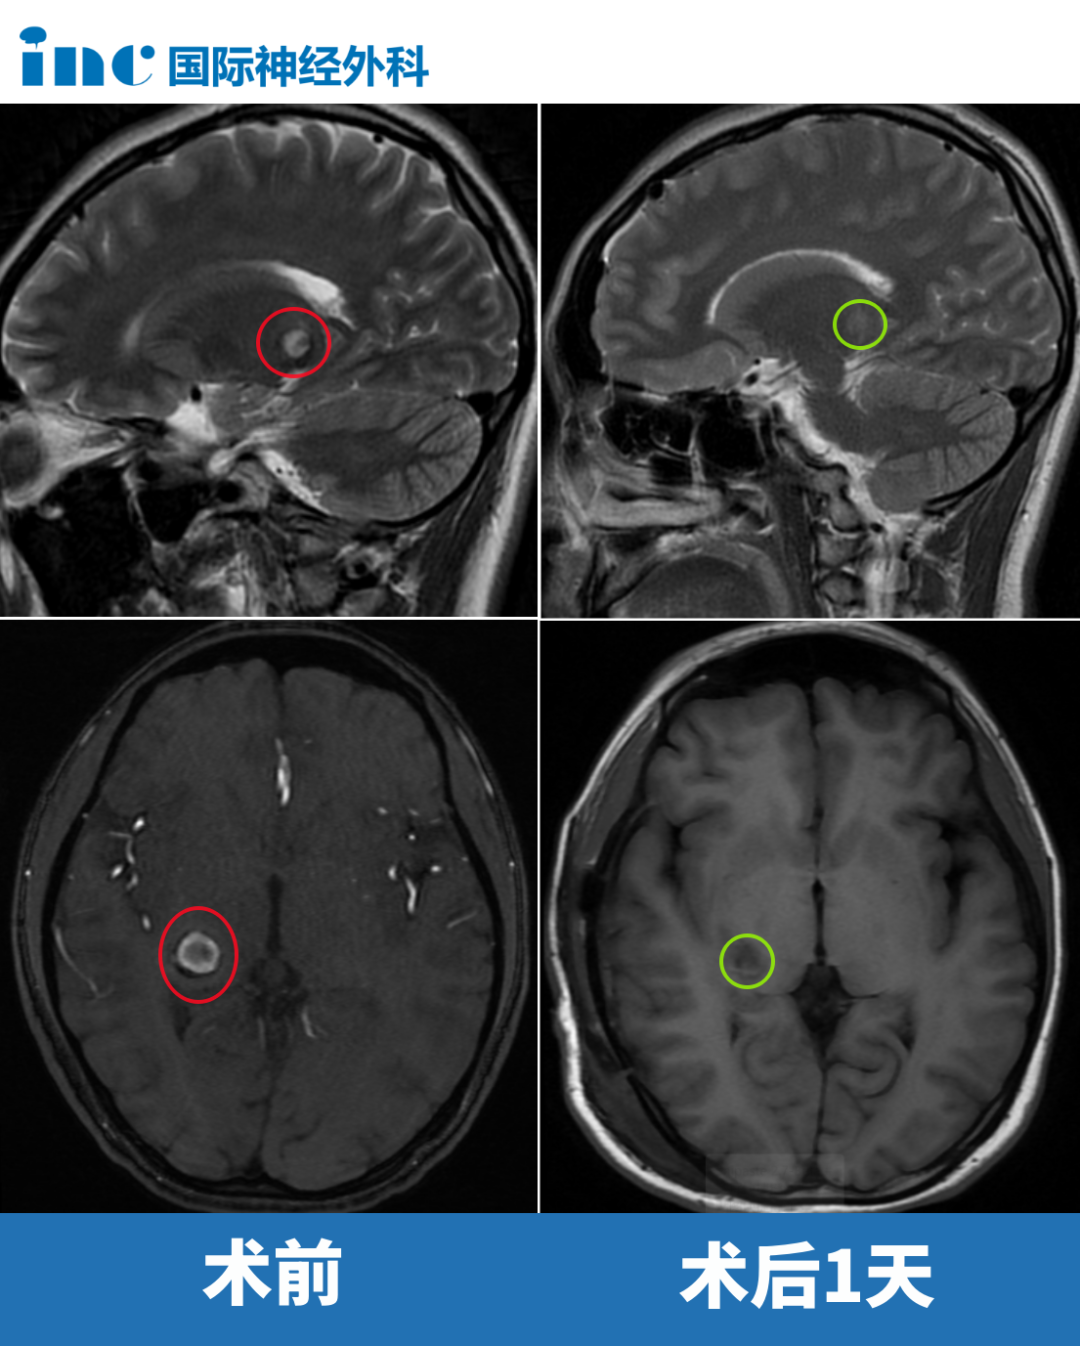

10歲男孩丘腦膠質(zhì)瘤

年僅10歲的左側(cè)丘腦占位性病變患兒,腫瘤呈彌漫性生長跡象,侵入腦實(shí)質(zhì)。開顱手術(shù)之路絕非坦途,任何細(xì)微的操作失誤,都可能引發(fā)嚴(yán)重的后果。幸運(yùn)的是,關(guān)鍵時刻,佑佑等來了“巴爺爺”。術(shù)后當(dāng)天,佑佑蘇醒后直接從手術(shù)室轉(zhuǎn)入普通病房。“寶貝,勇敢勇敢!”父母也一直鼓舞著佑佑。當(dāng)天查房時,佑佑可以握拳、抬腳。